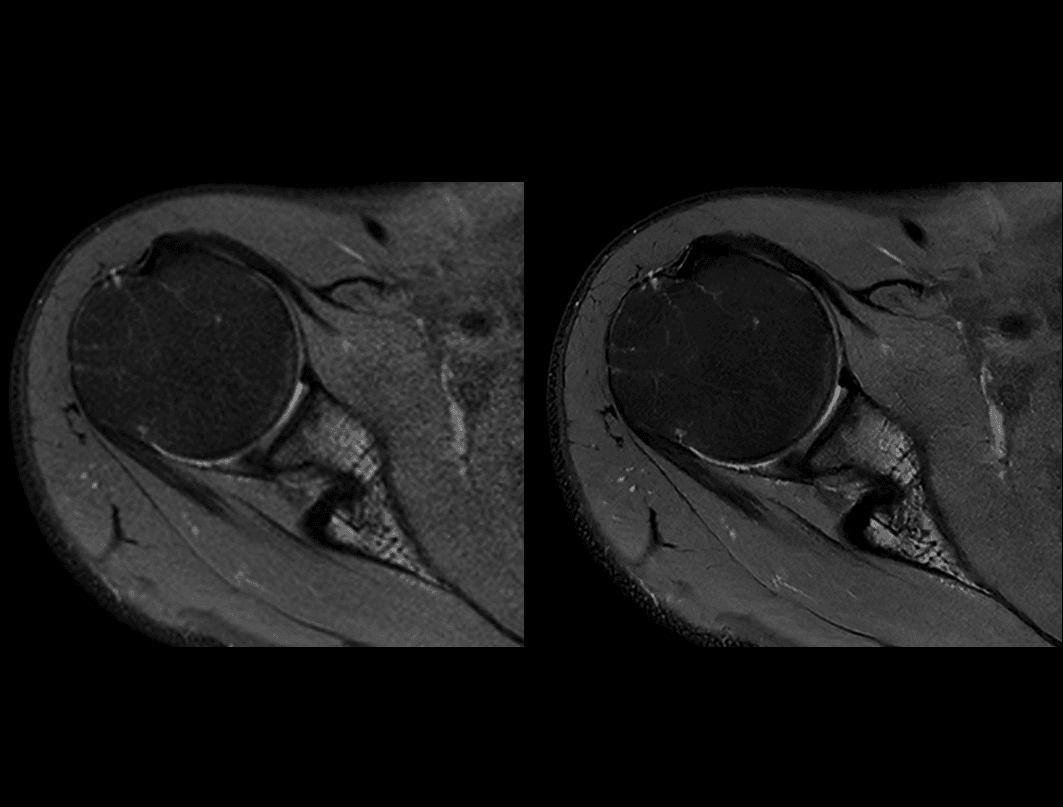

Umăr PDW FS

Comparație între tehnica convențională (2:56 min) și uAIFI DeepRecon™ (2:56 min) cu rezoluție de 0,29 × 0,29 × 3 mm³, demonstrând claritatea superioară a imaginilor obținute prin reconstrucția bazată pe AI.